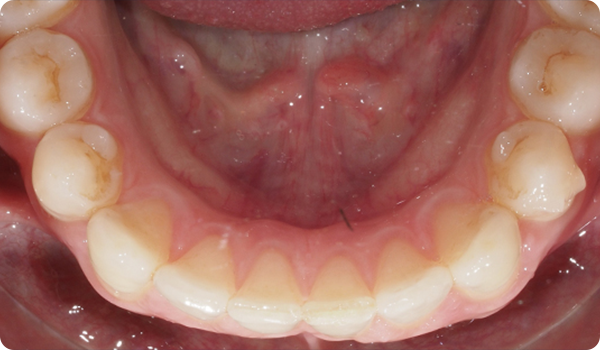

Sourires en place

Grâce à Right, vos patients obtiendront le sourire qu'ils souhaitent quand ils le souhaitent, de manière confortable et indétectable.

L'alignement des dents avec Right est la solution parfaite et la plus conservatrice pour les futurs traitements de blanchiment ou de facettes. Elle apportera la perfection au sourire du patient.